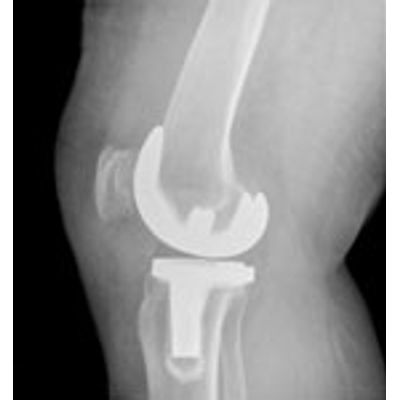

Advances in biomedical implant and device technology continue to present new challenges in the area of physical testing. Particle Size Distribution, Surface Area and Porosity measurement data are invaluable to the biomedical researcher. PTL partners with each client to design projects that provide this needed information while controlling the costs of research. Applications have included particle size analysis of wear particles in fluid submitted from implant fatigue studies and pore size analysis of tricalcium phosphate granules compressed into bone grafting media. Evaluation by photomicroscopy and mercury porosimetry of artifical ligament materials have provided insight to researchers on their products.Stay in the loop!